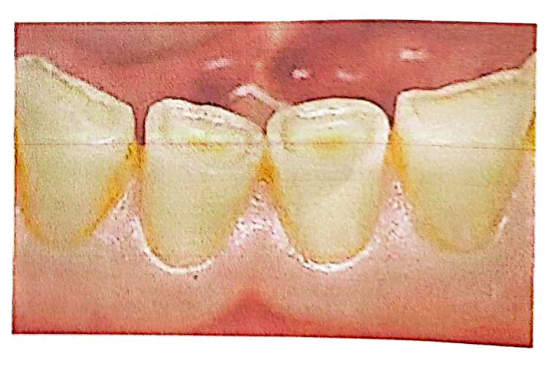

1. La gencive : Tissu épithélio-conjonctif divisé en trois zones :

- Gencive papillaire : logée dans l’embrasure, en dessous du point de contact

- Gencive marginale : entoure la zone cervicale de la dent à la façon d’un collier, s’étend du rebord marginal jusqu’à la gencive attachée dont elle est séparée par le sillon marginal. Elle n’adhère pas à la dent et forme la paroi molle du sulcus gingival (profondeur de 0.5 à 3 mm)

- Gencive attachée : large bande de gencive très adhérente à l’os sous-jacent (hauteur de 0.5 à 7 mm).

2. Le sillon gingivo-dentaire : Dépression de 0.5 à 3mm de profondeur qui entoure la dent, limitée par la surface dentaire et le revêtement épithélial interne de la gencive marginale.

3. La jonction dento-épithéliale : Frontière entre milieu interne et externe, perméable au fluide gingival. Les atteintes parodontales graves engendrent sa migration apicale.

4. L’espace biologique : Espace de 2mm entre le fond du sulcus et le sommet de la crête osseuse alvéolaire. Zone interdite à la limite prothétique.